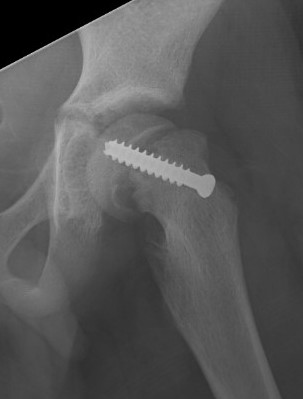

Subtrochanteric fracture

Subtrochanteric fracture likely causes by multiple drill holes / attempts

Cause

Too low screw entry

Multiple drill holes to get correct entry

Management

Intramedullary nail